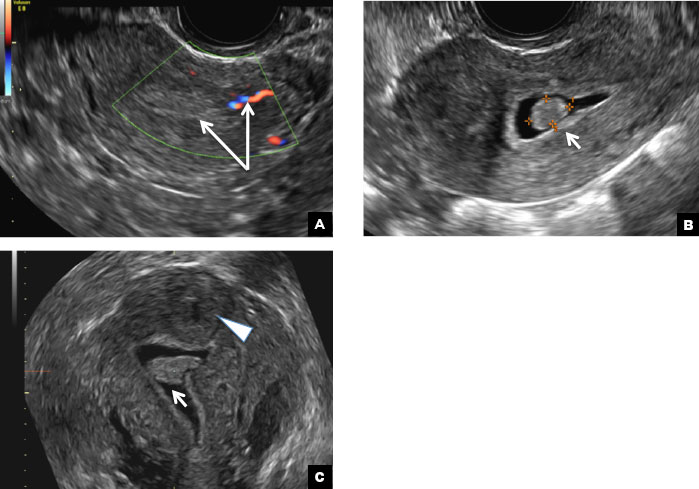

Endometrial polyp. (A) Transvaginal pelvic ultrasound of the uterus with color Doppler demonstrates a focal echogenic lesion with a vascular stalk (long arrows). (B) SHG shows a well-defined polypoid lesion, isoechoic to the endometrium, and protruding into the endometrial canal but still preserving the endometrial−myometrial interface (short arrow). (C) 3D SHG imaging shows the echogenic endometrial polyp (short arrow) and an incidental intramural fibroid in the fundus (arrowhead).